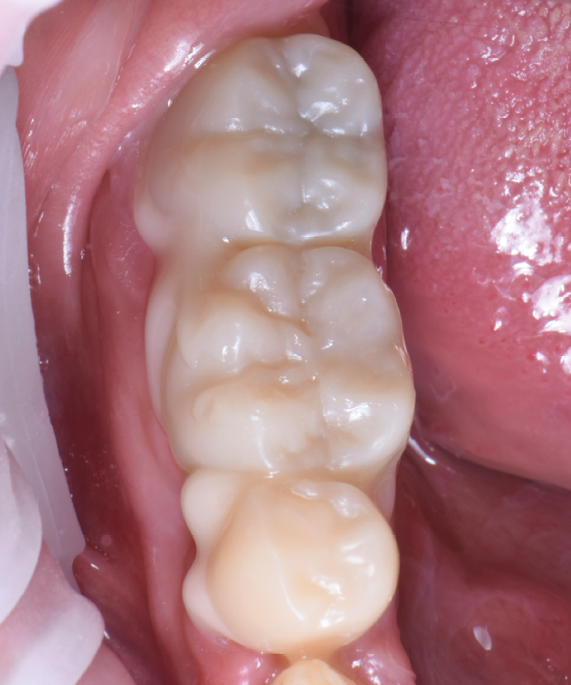

Au vu du contexte para-fonctionnel et de l’étendue de la perte tissulaire, des coiffes périphériques minimalement invasives ont été choisies afin de restaurer l’esthétique et la fonction. Actuellement, aucun consensus n’est fait sur le choix du matériau d’infrastructure à privilégier. Les matériaux hybrides usinables présentent des propriétés mécaniques, physiques et biologiques intéressantes en contexte d’usure sévère (e.g., module d’élasticité, résistance à la propagation de fêlures, facilité de réintervention). Une réhabilitation globale avec remontée de dimension verticale d’occlusion (DVO) par l’intermédiaire de coiffes composites renforcés en nano-céramiques est décrite.